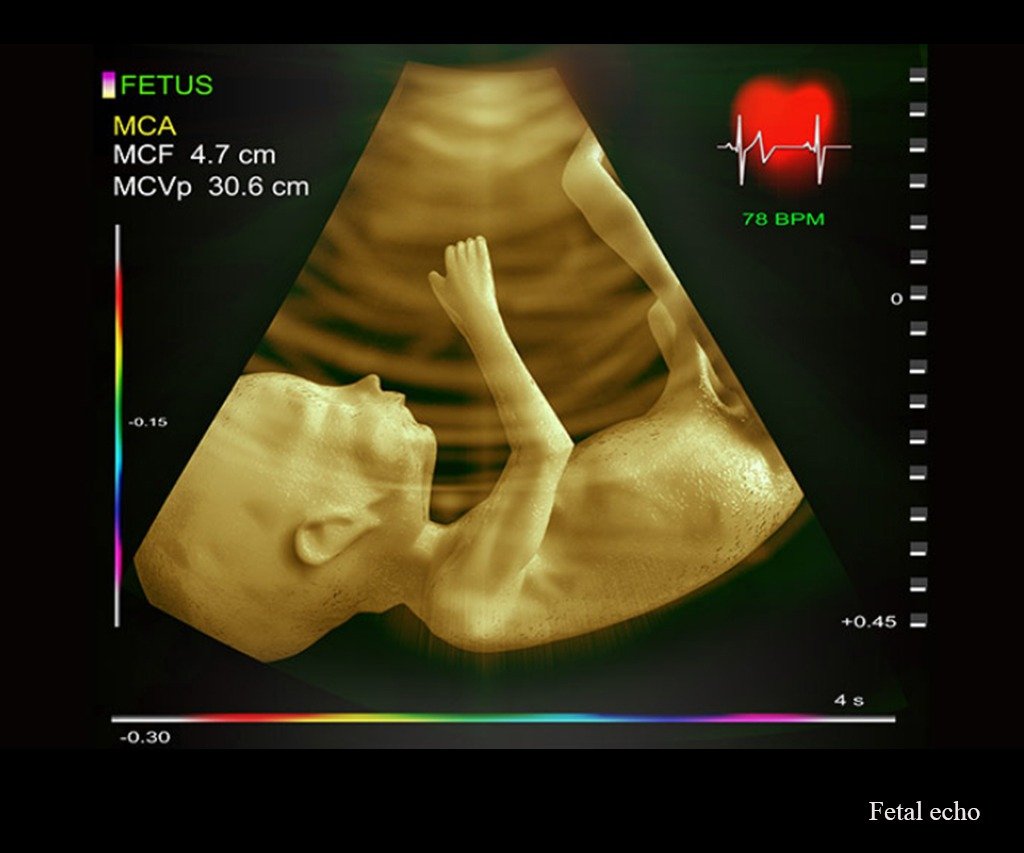

Fetal Echo

A fetal echocardiogram is a targeted ultrasound that assesses the structure and function of the baby’s heart. This scan is crucial if there’s a family history of heart defects, maternal health conditions, or abnormalities seen in previous scans. Our fetal cardiology team uses high-resolution imaging to detect congenital heart conditions early, allowing for informed planning and intervention if necessary.